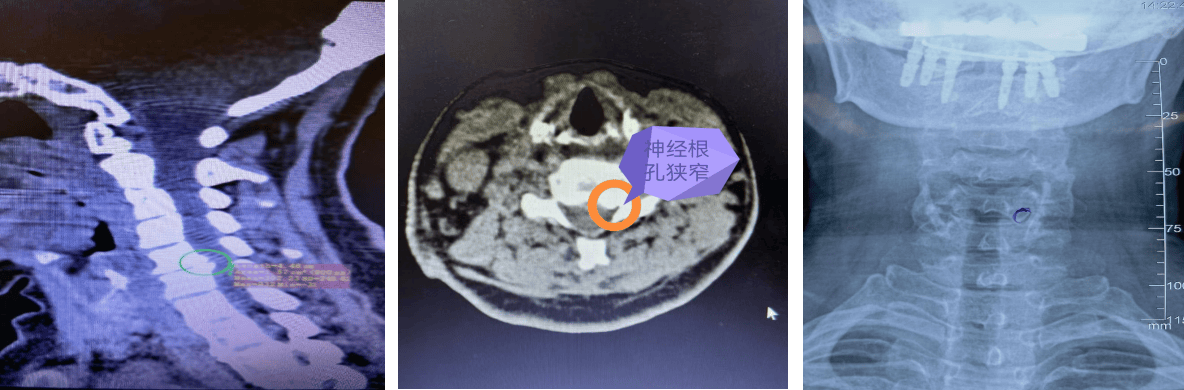

衢州骨伤科医院脊柱外科主任林俊接诊后,详细询问病史并结合CT、磁共振检查结果,确定郑女士的情况比较特殊,症状是由第5第6颈椎椎体后缘增生,压迫神经根引起的,增生的骨质其压迫C6左侧神经根孔,是典型的“神经根型颈椎病”表现 ,符合微创手术的适应症。

术中出血不到5毫升,切口长度约1厘米左右。术后患者左侧肩颈部和左上肢疼痛症状即刻得到明显缓解,经影像复查显示,保留了大部分侧块关节突关节,稳定性良好。